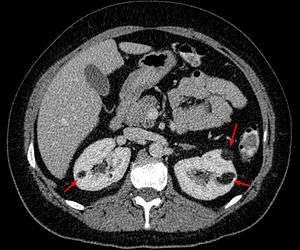

Angiomyolipoma in both kidneys (arrows) in computer tomography. The tumours are hypodense (dark) due to fat content | |

There are three methods of scanning that detect angiomyolipoma: ultrasound, CT and MRI. Ultrasound is standard and is particularly sensitive to the fat in angiomyolipoma but less so to the solid components. However it is hard to make accurate measurements with ultrasound. Computed tomography (CT) is very detailed and fast and allows accurate measurement. However, it exposes the patient to radiation and the dangers that a contrast dye used to aid the scanning may itself harm the kidneys. Magnetic resonance imaging (MRI) is safer than CT but many patients (particularly those with the learning difficulties or behavioural problems found in tuberous sclerosis) require sedation or general anaesthesia and the scan cannot be performed quickly.[2] Some other kidney tumours contain fat, so the presence of fat isn't diagnostic. It can be difficult to distinguish a fat-poor angiomyolipoma from a renal cell carcinoma[3] and a lesion growing at greater than 5 mm per year may warrant a biopsy in order to distinguish it from this form of cancer.[2]